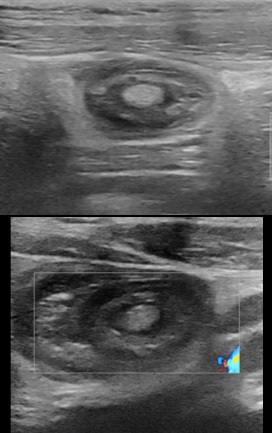

A 15-year-old male patient, with a history of intermittent abdominal pain, two episodes of bleeding considered to anal fissure, and of chronic constipation consulted twice in the emergency department for ileo-ileal intussusception more than a year apart. At the first presentation, the patient consult with the general condition preserved, apyrexia, bilious vomiting. The physical examination found pain in the right hypochondrium and sub umbilical, a soft abdomen, no tusks or palpable abdominal mass. The ultrasound performed found ileo-ileum intussusception without any sign of complication with the intussusception tube in the pelvic position (Figure1).